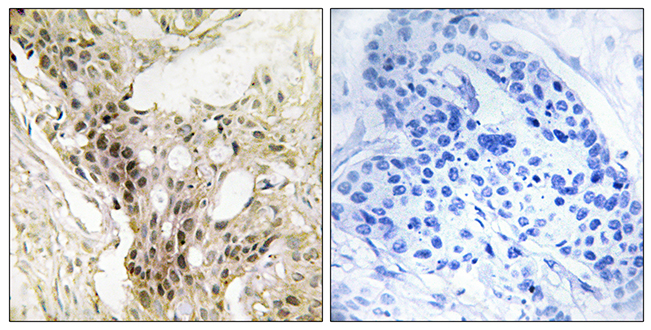

Anti-LAMA5 AntibodyA98865

ApplicationsELISA, ImmunoHistoChemistry

ReactivityHuman, Mouse

- SizePrice